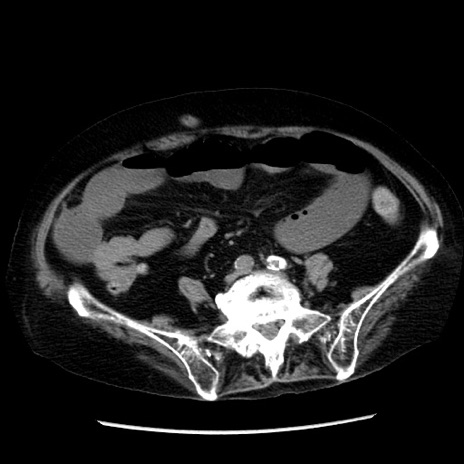

冠状断像